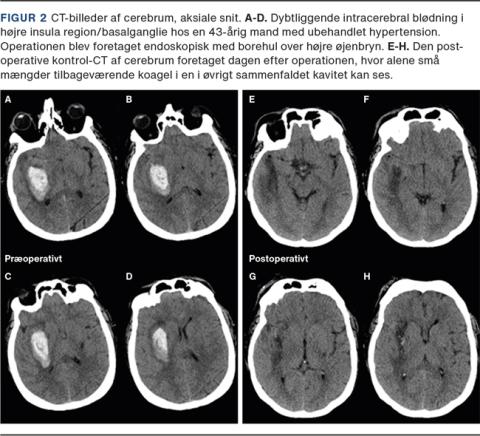

I Figur 2 og Figur 3 vises to sygehistorier med dybtliggende ICH i basalganglier, hvor begge er fjernet med endoskopisk operationsteknik. Begge patienter har haft et kort (24 timers) forløb i et neurointensivt afsnit, hvorefter neurorehabilitering kunne påbegyndes.

Billede